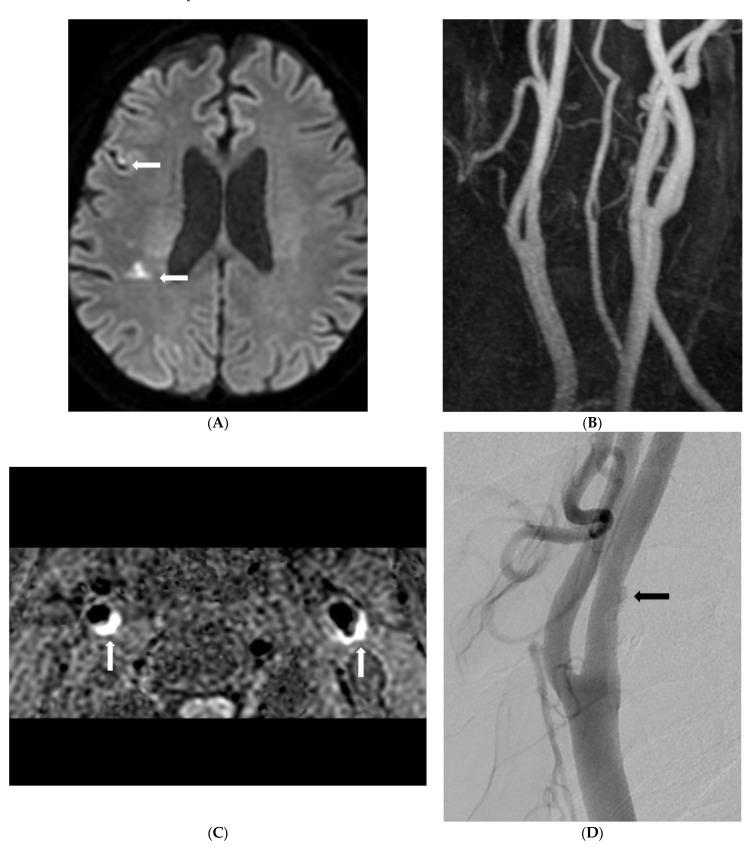

Background: To determine the prevalence of symptomatic nonstenotic carotid disease (SyNC) using simultaneous non-contrast angiography and intraplaque hemorrhage (SNAP) imaging for patients with acute stroke as an MR screen protocol and to assess imaging findings of carotid plaques. Patients and Methods: From May 2020 to October 2021, 2459 patients with suspected acute neurological symptoms were evaluated with brain diffusion-weighted imaging (DWI) and carotid SNAP imaging. We analyzed the degree of stenosis and intraplaque hemorrhage (IPH) using SNAP imaging. Prevalence of SyNC and risk factors for stroke in patients with SyNC were determined. We performed subgroup multivariate analysis between SyNC and other etiologies of stroke (non-SyNC). Results: Of 4608 carotid arteries in 2304 patients enrolled in this study, 454 (9.9%) plaques (both lesions in 128 patients) were found on SNAP imaging. Of these plaques, 353 (77.8%) showed stenosis of <50%. Of plaques with <50% stenosis, 47 (13.3%) patients had a territorial acute focal infarction. Seventeen (36.2%) were classified with embolic stroke of undetermined source (ESUS) and SyNC. High maximal wall thickness and carotid IPH were identified as influencing factors for SyNC. Conclusion: For patients with <50% stenosis and territorial infarction, SyNC is a relatively important source of stroke. Especially, high maximal wall thickness and carotid IPH are important risk factors for SyNC.

背景

采用同时进行的非对比血管造影和斑块内出血(SNAP)成像作为磁共振筛查方案,以确定急性卒中患者中症状性非狭窄性颈动脉疾病(SyNC)的患病率,并评估颈动脉斑块的影像学表现。患者与方法:2020年5月至2021年10月,对2459例疑似急性神经症状患者进行脑扩散加权成像(DWI)和颈动脉SNAP成像评估。我们使用SNAP成像分析狭窄程度和斑块内出血(IPH)情况。确定SyNC的患病率以及SyNC患者的卒中危险因素。我们对SyNC与其他卒中病因(非SyNC)进行亚组多变量分析。结果:在本研究纳入的2304例患者的4608条颈动脉中,SNAP成像发现454个(9.9%)斑块(128例患者存在两处病变)。在这些斑块中,353个(77.8%)显示狭窄程度<50%。在狭窄程度<50%的斑块中,47例(13.3%)患者发生了区域性急性局灶性梗死。17例(36.2%)被归类为不明来源栓塞性卒中(ESUS)和SyNC。最大管壁厚度和颈动脉IPH被确定为SyNC的影响因素。结论:对于狭窄程度<50%且发生区域性梗死的患者,SyNC是卒中的一个相对重要来源。特别是,最大管壁厚度和颈动脉IPH是SyNC的重要危险因素。